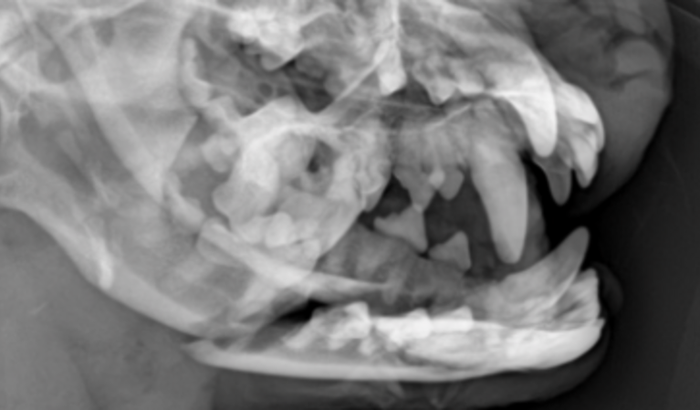

Olá, meu nome é Márcia pereira Afonso, sou mãe do Gold ( Lhasa Apso de 7 anos e 6 meses ), dou lar temporário a 4 cachorros sobreviventes de um incêndio no Alto Floresta, onde uma casa pegou fogo e infelizmente 26 animais faleceram, inclusive sua tutora. Esses 4 cachorros estão comigo a cerca de um mês e ontem 29/07/22 ocorreu uma briga entre um deles e o meu Lhasa, eu não estava presente e somente quando cheguei do serviço que vi o que aconteceu. Corri pro veterinário, já iniciamos os medicamentos que são muitos, foi feito um raio-x, o maxilar do Gold está quebrado e a fratura é exposta, ele precisa de cirurgia. Por isso estou aqui fazendo essa vaquinha, um apelo pra vocês meus amigos, familiares, conhecidos, amantes da causa animal, por favor, me ajudem a salvar o meu filho de quatro patinhas. Que Deus abençoe e devolva em dobro a vocês.